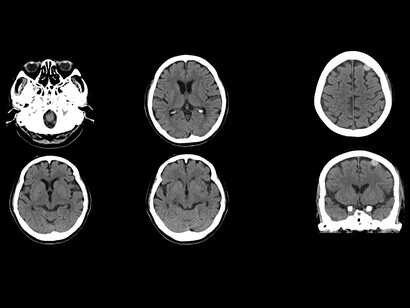

Es probable que también ordene análisis de sangre para detectar posibles causas subyacentes, como problemas de tiroides o hígado. Así como pruebas de neuroimagen (TAC o escáner, resonancia magnética nuclear y pruebas de medicina nuclear). Las pruebas de medicina nuclear rastrean el movimiento de dopamina en el cerebro y son conocidas de múltiples formas como SPECT, Datascan o DaT-SPECT y tomogammagrafía. La prueba utiliza marcadores radioactivos diseñados para rastrear la dopamina en el cerebro. Esto le permite al médico observar la liberación de este neurotransmisor en el cerebro de una persona e identificar las áreas cerebrales que la reciben o no atendiendo al brillo de dichas zonas.